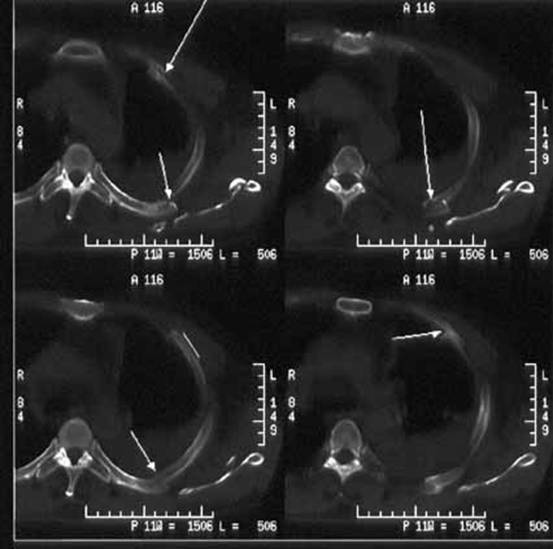

" p6 P6 K4 {0 e& g5 ^* KCT可以看成是“加强版”的X平片。由于X平片摄影时所有组织的影像都重叠在一起,大大降低了分辨率,人们发明了X线断层扫描的办法,将薄至数毫米厚的组织影像呈现出来,大大减少了组织重叠影,看到很多平片看不到的细节,减少了漏诊误诊。; _7 ^: N+ n* S8 F

【CT示例】这是左肩胛骨骨折,合并左第2-5肋骨骨折的CT图像。[2]